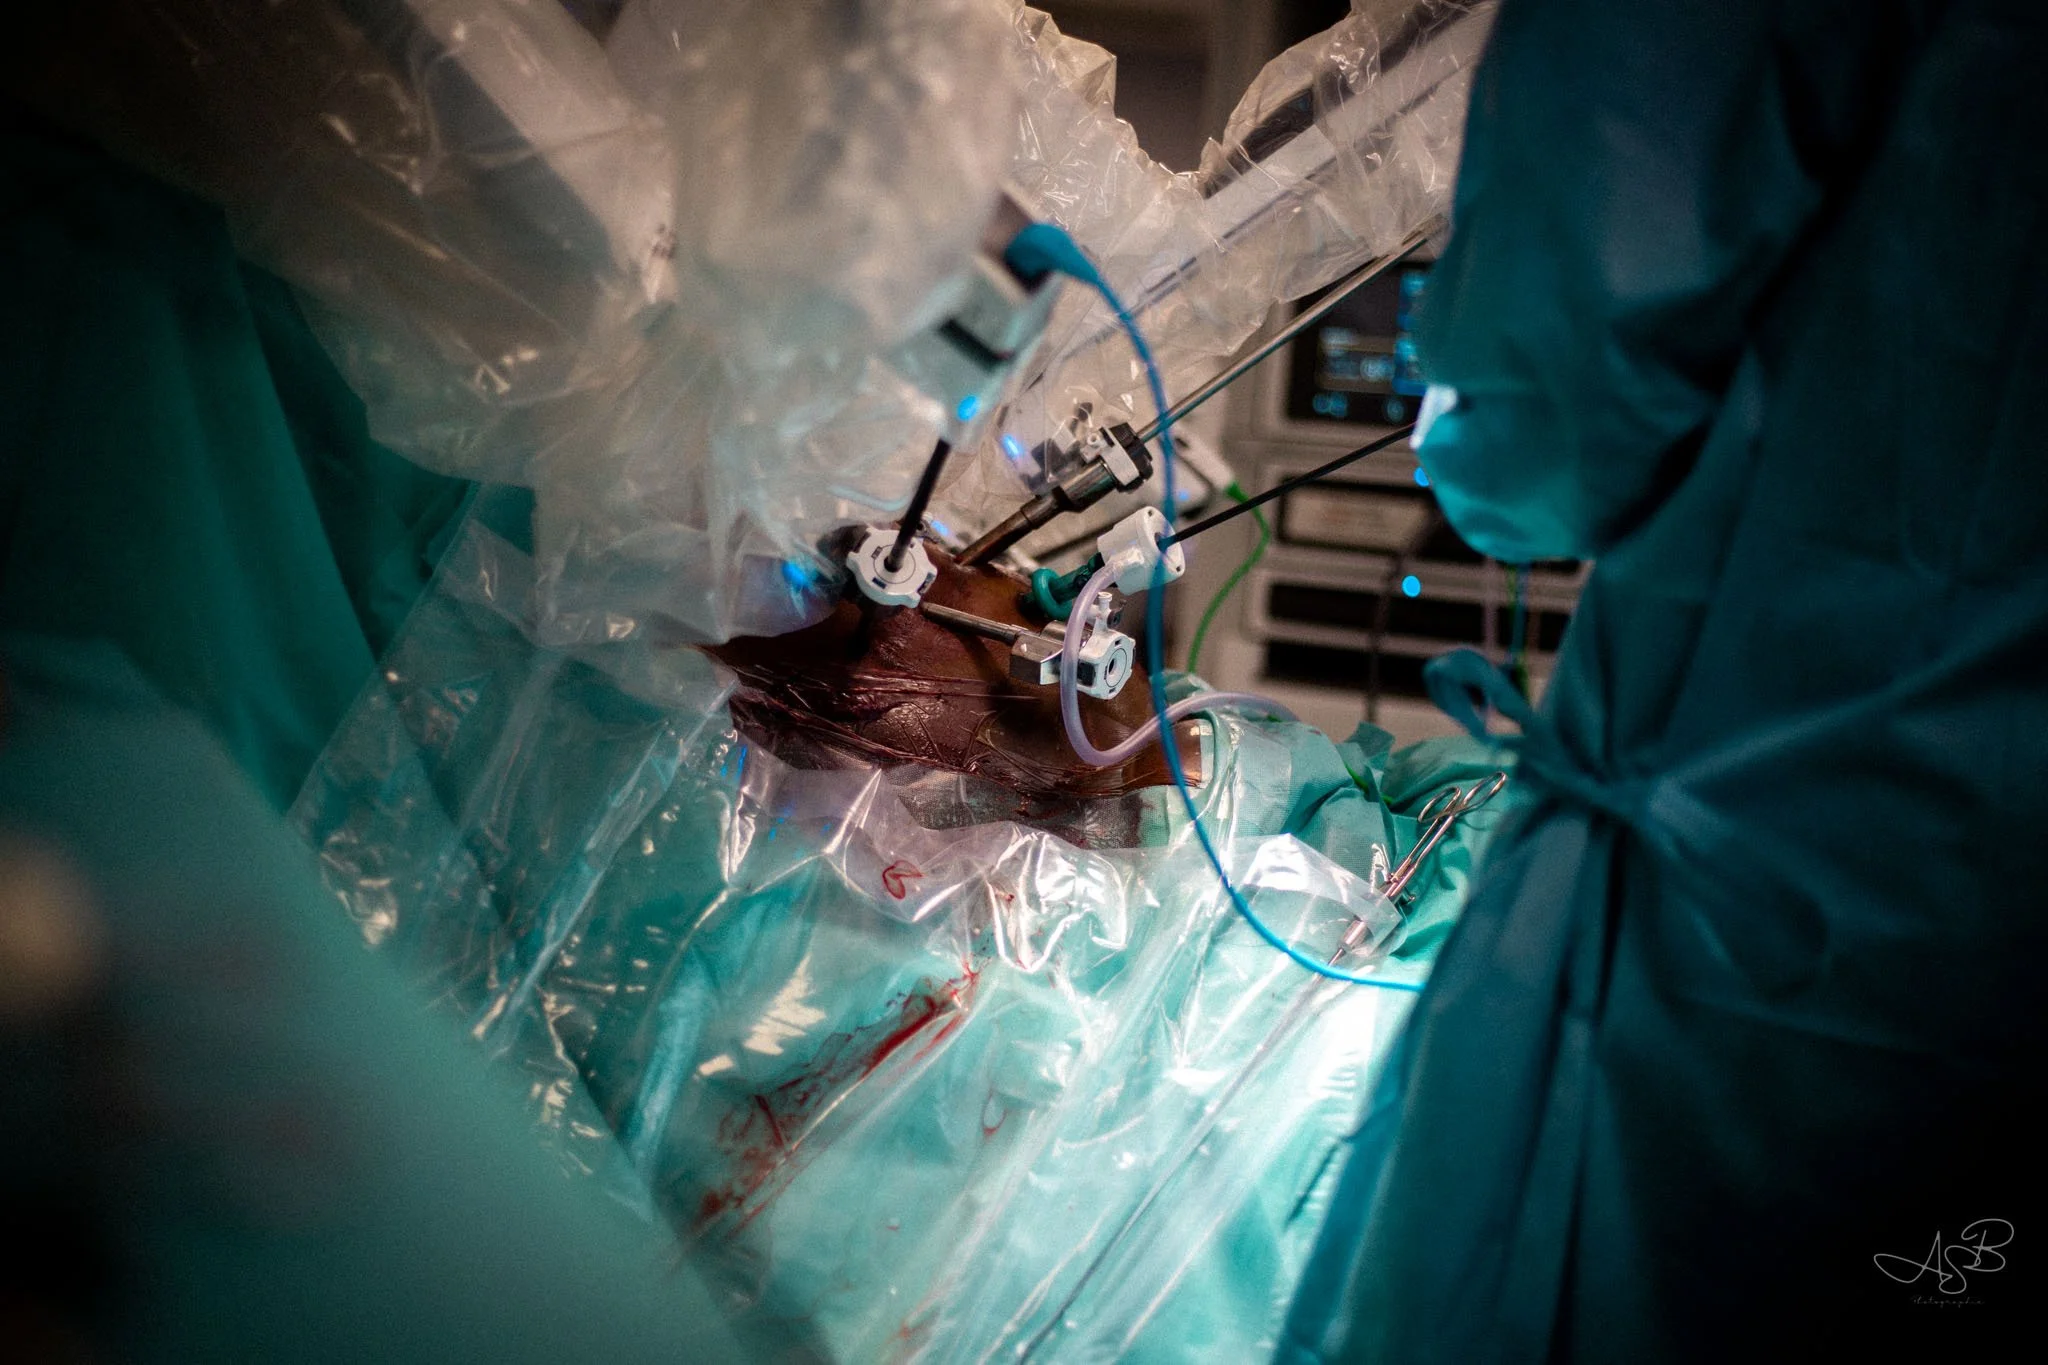

Corps en Silence.

L’exploration des tensions du corps féminin, là où la douleur se révèle quand les mots eux ne suffisent plus.

Partie 2 (bas de page) : La chirurgie des Femmes